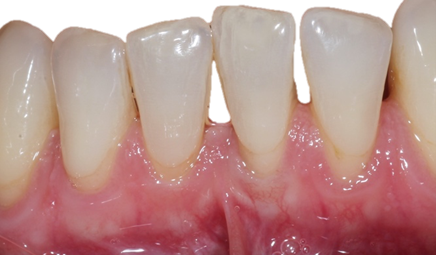

![]() | ![]() |

| Free gingival graft surgery’ to thicken gum and prevent further recession | Gum recession surgery in an aesthetic site |